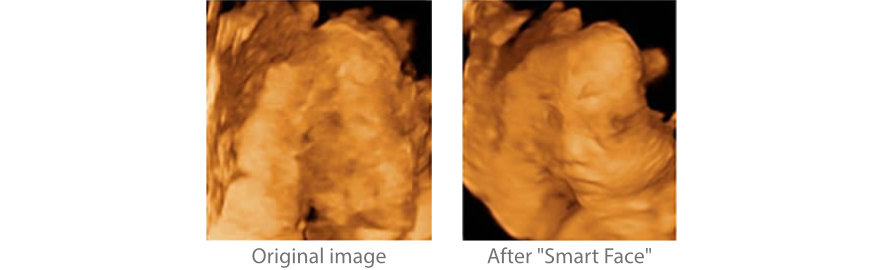

Smart Face

El nuevo Z50 proporciona una optimizaciĂłn rĂĄpida e inteligente del rostro del feto con una simple operaciĂłn de un solo toque. Puede eliminar de forma inmediata las oclusiones en los datos de volumen, excluir el ruido no deseado y generar una visiĂłn Ăłptima del rostro fetal con un mĂnimo de esfuerzo.